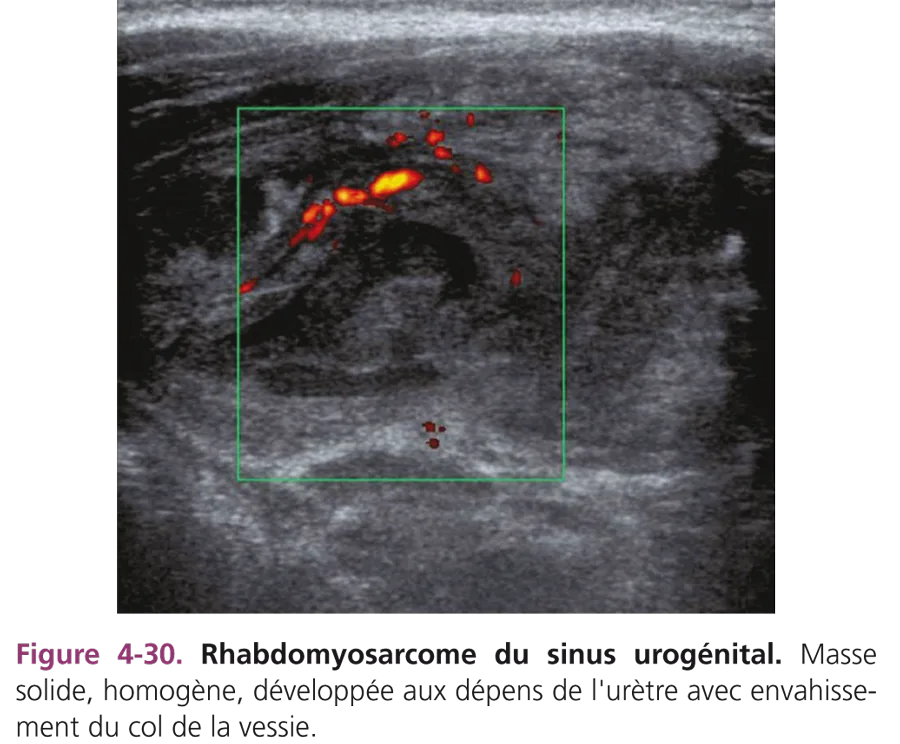

Abcès pelviens

Le plus souvent d’origine appendiculaire, ils peuvent compliquer une infection d’un diverticule de Meckel ou une maladie de Crohn. Ces collections, de topographie intervésicorectale, sont hypoéchogènes, hétérogènes, à paroi épaisse et irrégulière. Il peut s’y associer un épanchement liquidien du cul-de-sac de Douglas. Les données cliniques et biologiques (NFS [numération-formule sanguine], CRP [C-réactive protéine]) aident à porter le diagnostic. En cas de localisation sus-vésicale et médiane de la lésion, il faudra évoquer un kyste de l’ouraque surinfecté (fig. 4-29).

Rhabdomyosarcomes pelviens

Ce sont les tumeurs mésenchymateuses malignes les plus fréquentes chez l’enfant. Les formes pelviennes sont souvent observées dans la petite enfance. Les rhabdomyosarcomes du sinus urogénital se développent aux dépens du trigone vésical, de la prostate, du vagin, de l’utérus et des paramètres. Les signes urinaires d’appel sont fréquents : dysurie, rétention d’urine, hématurie. Parfois, le diagnostic est évoqué devant une masse polypoïde à la vulve (forme botryoïde) chez une fillette ou une grosse bourse chez un petit garçon. L’échographie montre une masse intervésicorectale basse, échogène, lobulée, en apprécie le volume et l’extension à la paroi vésicale (fig. 4-30) et précise le degré d’obstruction du haut appareil urinaire.